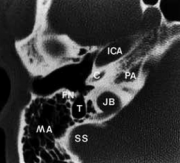

FN – facial nerve (სახის ნერვი)

TT – tensor tympani (აპკის დამჭიმავი)

C – cochlea (ლოკოკინა)

U – utriculus (უტრიკულუსი)

CN – cochlear nerve (კოხლეარული ნერვი)

VN – vestibular nerve (ვესტიბულარული ნერვი)

CP – cochleariform process (კოხლეარული მორჩი)

M – maleus neck (ჩაქუჩის ყელი)

L – long process of incus (გრდემლის გრძელი მორჩი)

S – stapes (უზანგი)

TM – tympanic membrane (დაფის აპკი)

EAC – external auditory canal (გარეთა სასმენი მილი)

TMJ – temporo mandibular joint (ყბის სახსარი)